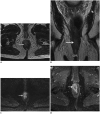

Although a rare disease, anal cancer is increasingly being diagnosed in patients with risk factors, mainly anal infection with the human papilloma virus. Magnetic resonance imaging (MRI) with external phased-array coils is recommended as the imaging modality of choice to grade anal cancers and to evaluate the response assessment after chemoradiotherapy, with a high contrast and good anatomic resolution of the anal canal. MRI provides a performant evaluation of size, extent and signal characteristics of the anal tumor before and after treatment, as well as lymph node involvement and extension to the adjacent organs. MRI is also particularly helpful in the assessment of complications after treatment, and in the diagnosis for relapse of the diseases.